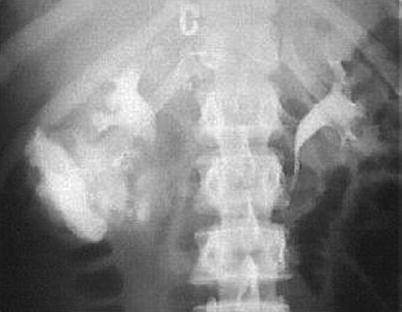

Fig. 20.2

Urinoma (white arrow) detected on IV contrast-enhanced CT scan after a stab wound to the right upper quadrant. The knife went through the right portion of the liver into the right kidney, where it perforated the major collection system

Initially, an early phase intravenous contrast CT scan of the abdomen and pelvis is performed. This investigation is highly sensitive in diagnosing parenchymal or vascular injuries to the kidneys as well as in detecting associated injuries (Fig. 20.1). To fully evaluate the collection system, a second CT scan is performed, approximately 10 min after intravenous contrast injection. This technique is known as CT intravenous pyelography (CT-IVP). These delayed-phase images are highly sensitive in diagnosing parenchymal injuries and proximal urine leaks or urinomas and in confirming bilateral functional renal moieties (Fig. 20.2). However, with a low sensitivity of 37 % to detect subtle ureteral injuries, small leaks at this location might be missed. Nevertheless, failure of the distal ureter to opacify on a contrast-enhanced CT scan should raise concern of an injury and should lead to further investigations or intraoperative evaluation of the affected ureter.